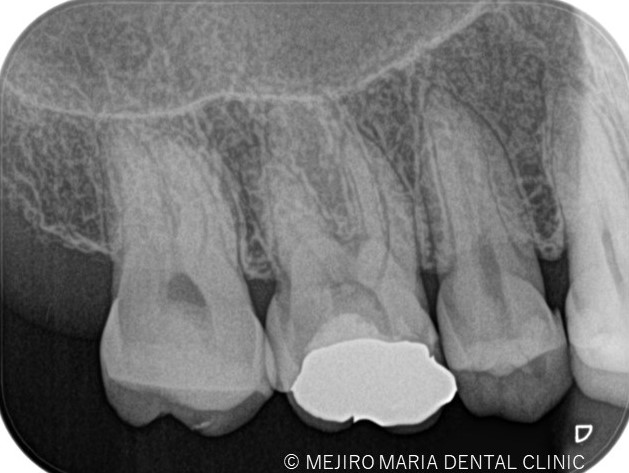

レントゲンの画像

歯髄が不可逆性歯髄炎なのか、可逆性歯髄炎なのかを確実に診断するためには組織切片のサンプルが必要になるため、事実上不可能です。そのため、歯髄の診断では冷たいものや温かいものなどに対する歯髄の反応を見極めることが重要になります。レントゲン、触診、温度診などの診査結果を総合的に踏まえて、現在の歯髄の状況を診断するためには、十分に診査時間を確保することが必要になります。